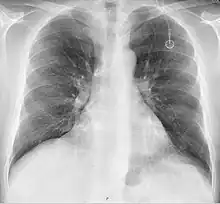

A follow-up on a chest radiograph can immediately detect complications associated with the procedure such as pneumothorax, hemothorax and malpositions of the catheter. However, routine chest radiography is not needed due to the low complication rates associated with the procedure. The chest radiograph is only done if there is clinical suspicion of a complication.[4]

Ports can be put in the upper chest or arm. The exact positioning itself is variable as it can be inserted to avoid visibility when wearing low cut shirts, and to avoid excess contact due to a backpack or bra strap. The most common placement is on the upper right portion of the chest, with the catheter itself looping through the right jugular vein, and down towards the patient's heart.